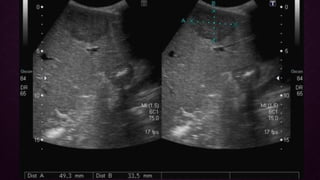

ECOGRAFIAECOGRAFIA

• Hígado pequeño HCC focal aparece hipoecoico en comparación con el hígado

normal

• Las lesiones más grandes son heterogéneas (fibrosis, cambios grasos, necrosis y

calcificación)

• Puede observarse un halo periférico de hipoecogenicidad (grasa)

• El HCC difuso puede ser difícil de identificar o distinguir de la cirrosis de fondo

ECOGRAFIAECOGRAFIA • Hígado pequeñoHCC focal aparece hipoecoico en comparación con el hígado normal • Las lesiones más grandes son heterogéneas (fibrosis, cambios grasos, necrosis y calcificación) • Puede observarse un halo periférico de hipoecogenicidad (grasa) • El HCC difuso puede ser difícil de identificar o distinguir de la cirrosis de fondo